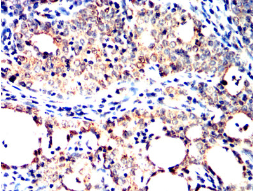

SH2B2 Mouse Monoclonal antibody[5E117]

AC3484 SH2B2 Mouse Monoclonal antibody[5E117] 100ug $367 10days

AC3484 SH2B2 Mouse Monoclonal antibody[5E117] 200ug $660.6 10days

Immunogen :   Purified recombinant fragment of human SH2B2 (AA: 497-676) expressed in E. Coli.

IHC    1/200 - 1/1000